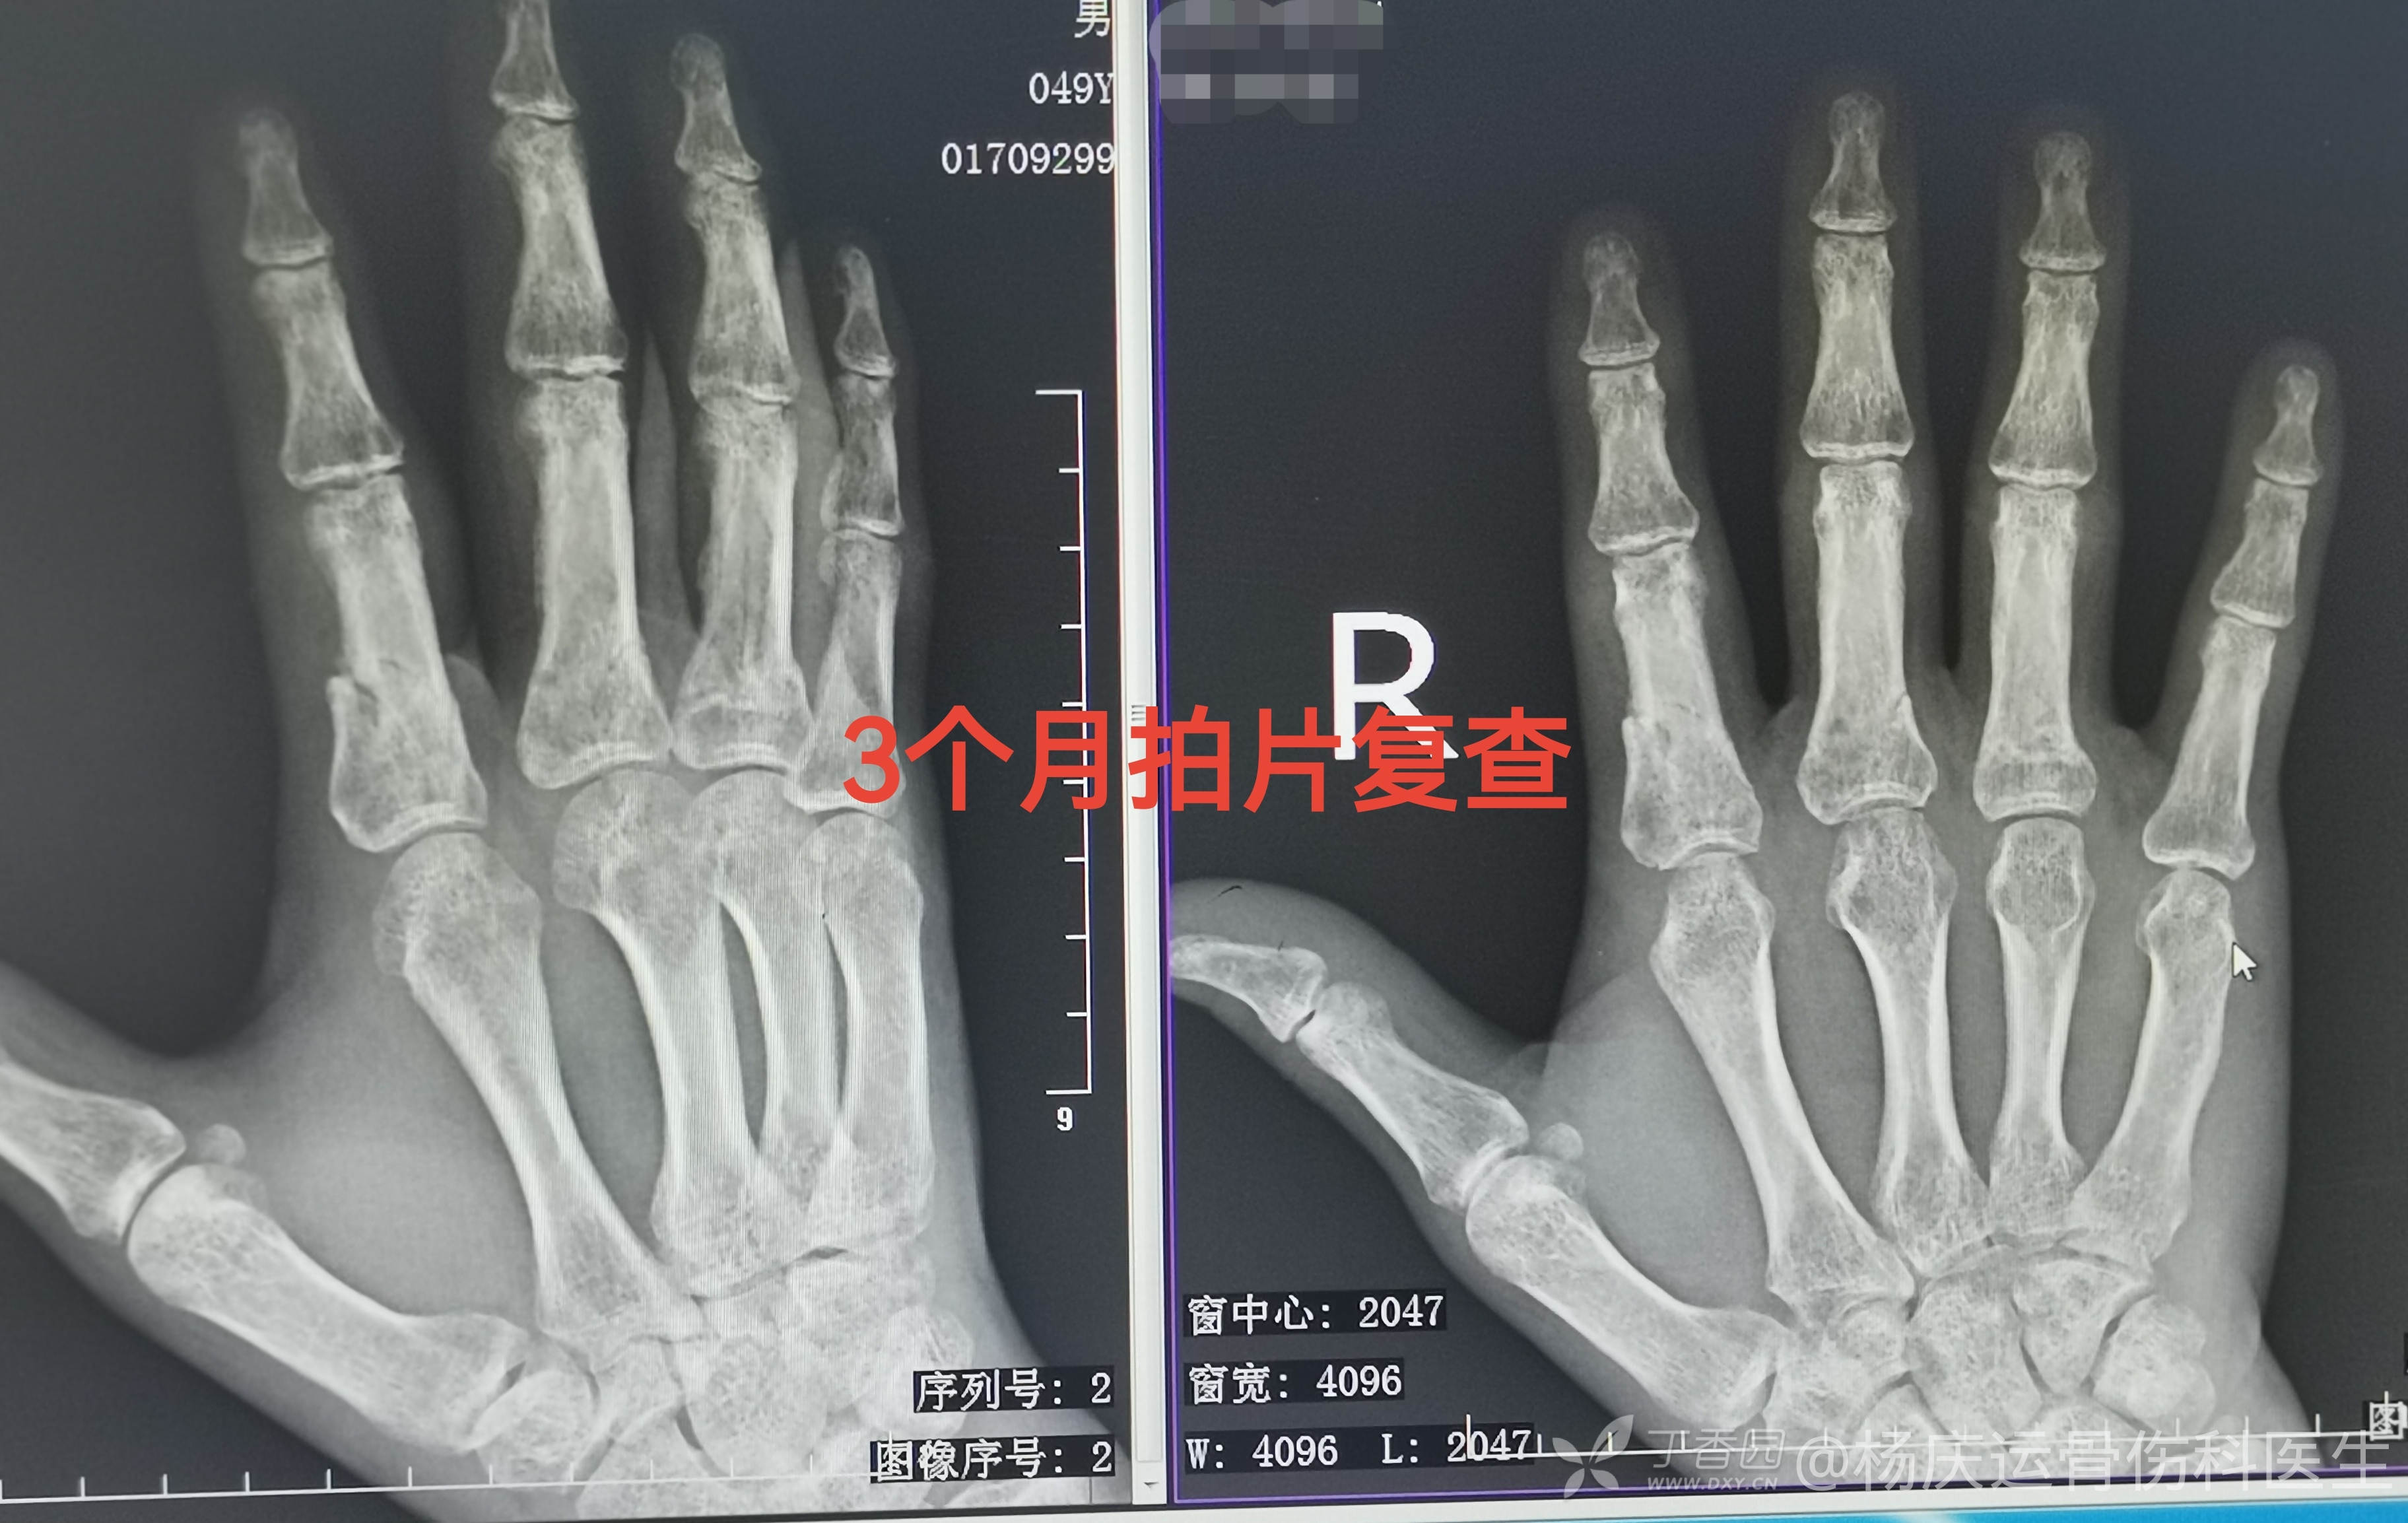

3个月拍片复查